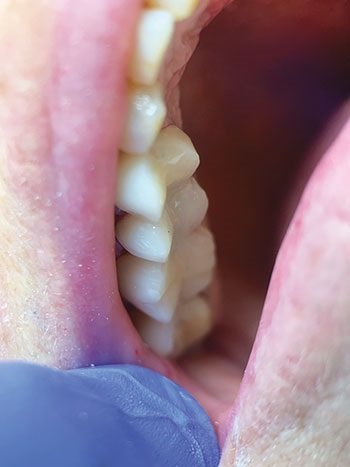

A non-eugenol temporary cement was used to adhere the temporary bridge to the prepared teeth, as non-eugenol cement is easier to remove than resin-based cement (Figs. 7 and 8). The entire appointment took 1.5 hours. The patient scheduled an appointment to return in eight weeks for a digitally scanned dental impression and to begin procedures for a permanent fixed bridge.

Fig. 7: Access Crown temporary three-unit bridge seated with noneugenol temporary cement.

Fig. 8: Final seating of Access Crown temporary bridge; labial-occlusal view.